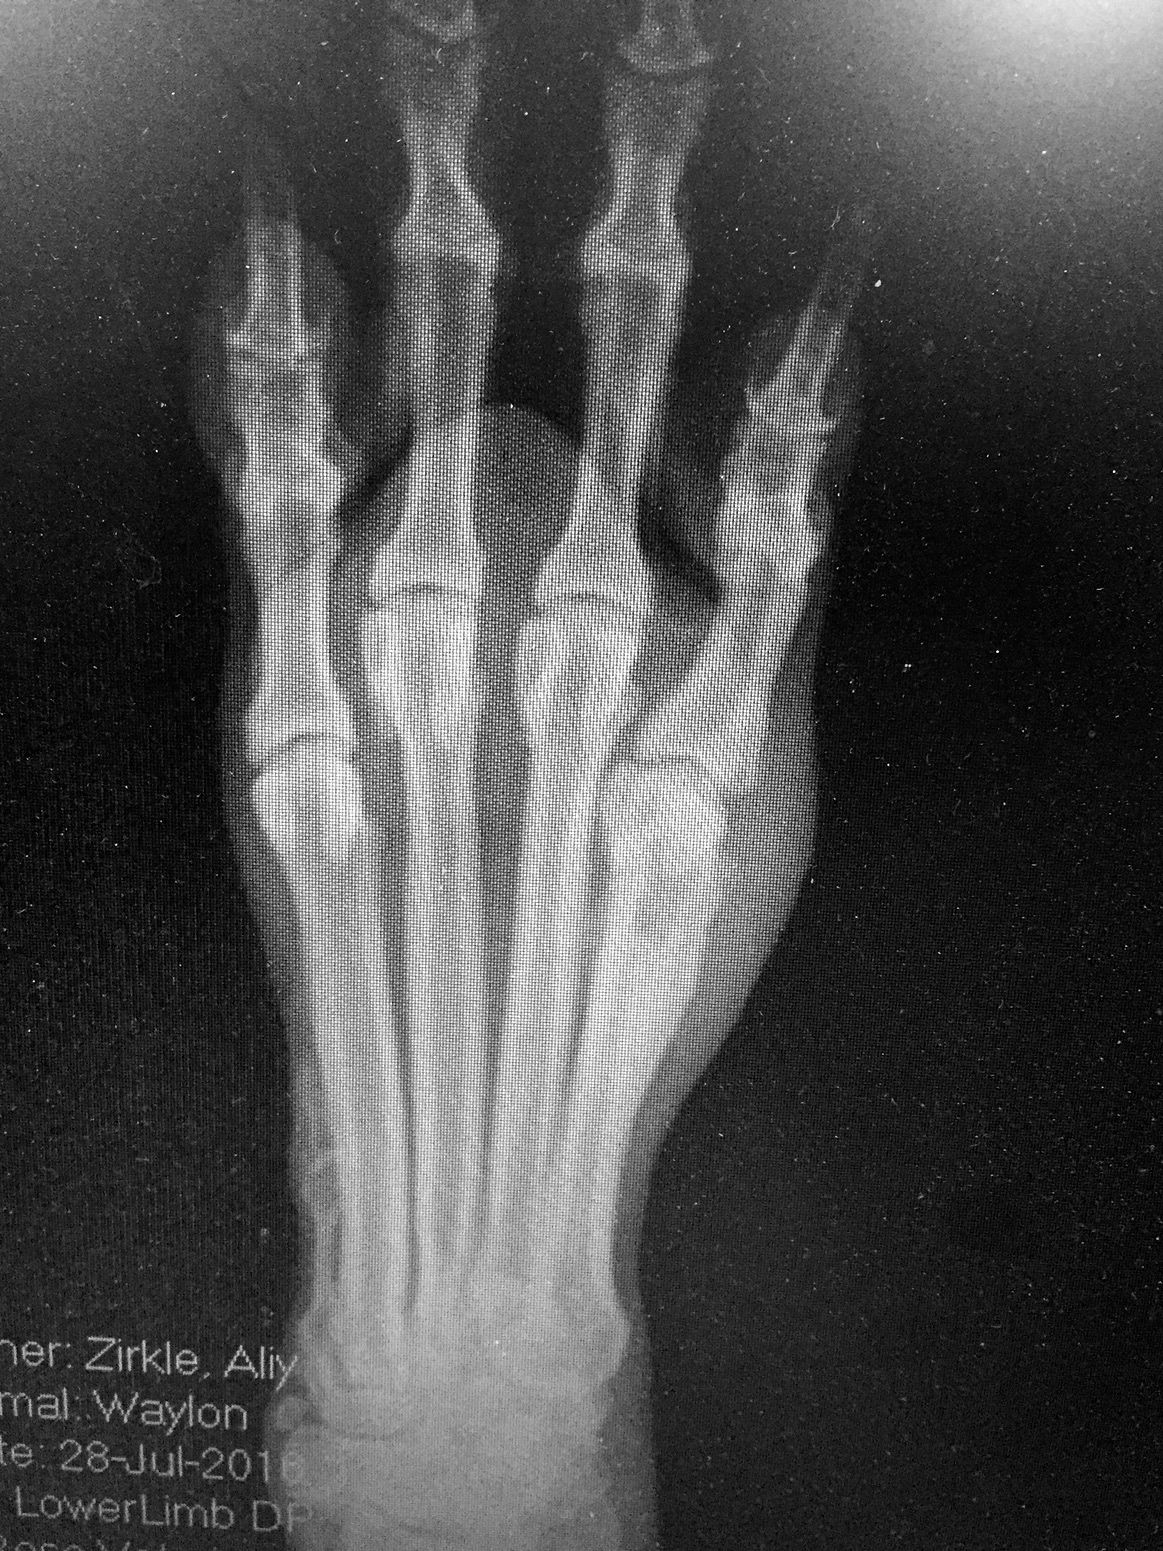

Waylon ended his 2016 racing season with a superb 3rd place Iditarod finish. At first, he seemed to recover from any trauma that might have occurred and during the Springtime he was the happy-go-lucky guy that we all know. But at mid summer, Waylon began limping on his front right foot. We did an X-ray of his paw and Dr Rose seemed to think the issue was either a serious bone infection in his small toe or… cancer.

We moved him out of the yard and into the dog room (or the “big” house) for a month while on several strong antibiotics and anti inflammation drugs. When we went for a follow up exam and took another series of X-rays, they showed zero changes. There were still signs of bone degradation and no improvement. He was asleep during the X-rays, in order to manipulate his toe position. So Dr Rose prodded his toe with a needle to see if there was fluid in the enlarged digit. When she did this the toe bone broke!! We were very surprised. She had to then immediately amputate the toe — we couldn’t leave him with a broken toe that would never heal — and there were really no other acceptable alternatives. So, Waylon came home 3-toed.

“The Rehab Room”; Waylon PRE surgery X-ray; Aliy POST surgery X-ray.